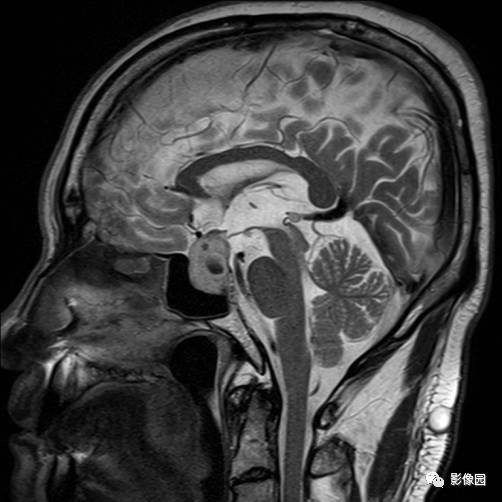

独孤求败:诊断为垂体瘤,蝶鞍扩大,鞍底下陷,鞍内见突向鞍上生长的团块状异常信号,T1WI呈等及稍高信号,T2WI呈等及低信号,增强扫描病灶呈明显不均匀强化;垂体柄显示不清,视交叉受压上抬。

lovethemoon:这不是颅咽管瘤,而是垂体瘤,颅咽管瘤时可见正常的垂体结构,此患者看不到正常的垂体结构,病变内短T1短T2异常信号是出血,垂体瘤合并了出血,颅咽管瘤囊变时的信号一般是长T1长T2。